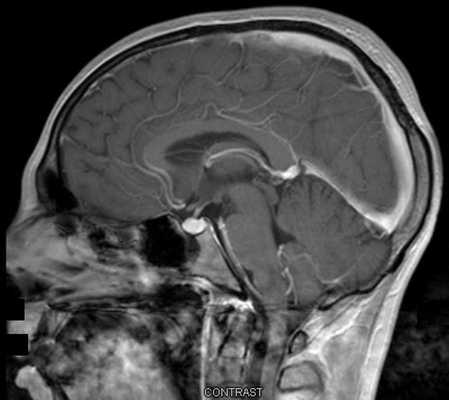

МРТ гипофиза с контрастом. После введения контрастного вещества в гипофизе происходит его накопления и он выглядит светлым. Только участок опухоли не накапливает контрастное вещество и выглятит темным (стрелка).

МРТ гипофиза до и после операции по удалению макроаденомы гипофиза